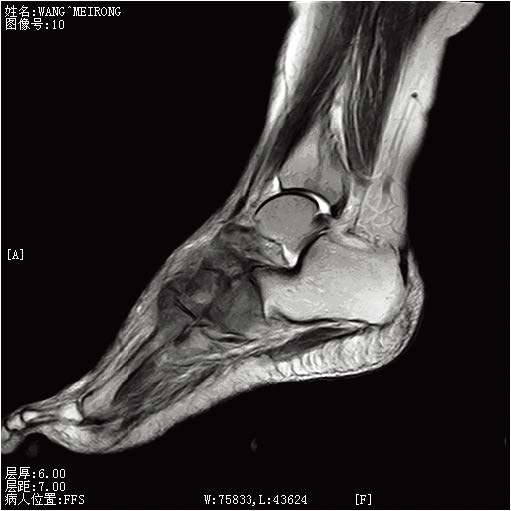

1 临床资料患者,女,49岁。主诉:月经紊乱1年,接触性阴道出血1年。妇科检查:外阴:阴毛呈女性分布,已婚已产式;阴道:通畅,黏膜光滑,穹隆消失;宫颈:结节状,直径5 cm,质糟脆,触血阳性;宫体:平位、大小正常、活动度好;附件:双侧附件区未触及异常肿物;宫旁:双侧宫旁组织结节与盆壁无间隙,弹性差。行宫颈活检辅助检查:鳞状细胞癌Ⅱ级,见图 1。彩超:右肾集合系统分离、宫颈占位、双肾积水、右侧输尿管扩张。盆腔MRI:宫颈处团块状等T1等T2信号肿物影,信号较均匀,境界不清,结合带消失。肿物侵及宫体,宫颈浆膜面模糊,肿物大小范围约4.3cm×9.0 cm。诊断:宫颈鳞癌Ⅲb期结节型。采用调强适形放疗,完成 PTV(planning target volume):DT 54 Gy/30 f,每次1.8 Gy,每周5次。放疗期间给以顺铂100 mg增敏(10 mg,静脉注射,1天1次,共10次)。行腔内后装放疗6次,A点剂量42Gy。放疗后采用PF[顺铂(50 mg/m2)+5-氟尿嘧啶(750 mg/m2)]方案全身化疗3周期。宫颈局部肿物消除满意,但治疗结束后14月出现阴道外口结节,直径2 cm。肿物活检:低分化癌。阴道转移诊断明确。行阴道结节插植放疗2次,剂量20Gy,并局部注射5-氟尿嘧啶3次,每次500 mg。采用吉西他滨+顺铂方案化疗2疗程治疗结束。15月后出现右脚肿胀、疼痛。ECT检查:全身骨骼显像清晰,结构完整,右侧足背骨可见异常放射性分布浓聚区,见图 2。核磁:右足部分跖骨、舟骨、距骨及部分根骨骨质破坏,呈长T1长T2信号改变,抑脂序列呈高信号,边界模糊,周围见软组织肿物,边界不清,关节间隙消失,见图 3。考虑右足骨转移。采用6 MV-X行右足部放疗,对穿照射,每野150 cGy/次,共10次。期间给予唑来膦酸4 mg每月1次静脉滴注,并给予恩度靶向治疗、口服药物镇痛等,疼痛较前减轻。17月后胸部CT提示:左肺下叶见数个结节影,最大者直径约0.9cm,边界清,轻度强化,考虑肺转移。采用紫杉醇+奥沙利铂方案化疗6次。从发病到死亡患者总生存期37月,骨转移后生存期22月。